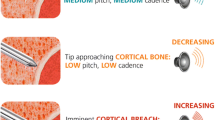

CTV identification protocol (Fig. 4 and supplementary video: “coracoid tunnel view”):

CTV protocol for fluoroscopy imaging: a view scapula in radiographic anterior–posterior view: identify the glenoid fossa, coracoid, acromion, scapular notch, superior scapular border, medial border, inferior border and scapula spine; b align viewing angle in cephalad direction until oval shaped tunnel appears; c adjust viewing angle until glenoid fossa is parallel to drilling direction; d the crosshair marks the optimal screw position

View scapula in radiographic anterior–posterior view: identify the glenoid fossa, coracoid, acromion, scapular notch, superior scapular border, medial border, inferior border and scapula spine.

Change viewing angle in cephalad direction until oval shaped tunnel (= coracoid tunnel) is projected between coracoid tip, glenoid fossa, scapular notch and superior scapular border.

Adjust viewing angle until glenoid fossa is parallel to drilling direction. Make sure that superior scapular border is kept superimposed into roughly one line.